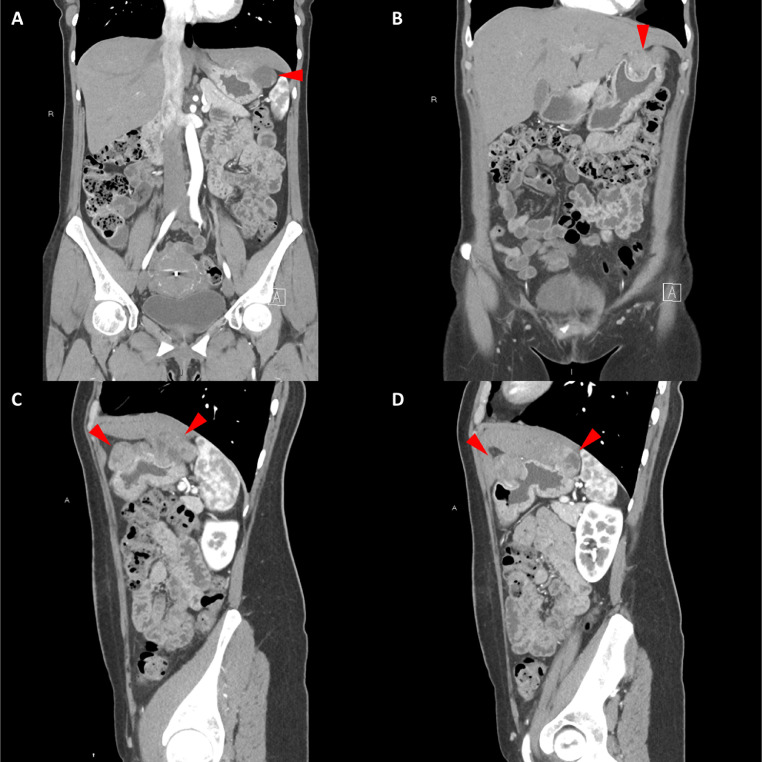

Fig. 3

圖 3:多個胃腸道間質瘤的冠狀和矢狀圖像。 (A 和 B)冠狀動脈相對比增強 CT 圖像顯示胃賁門產生的外生性腫塊。 (C 和 D)矢狀動脈相位對比增強圖像顯示腫塊的異質性和外生結構。